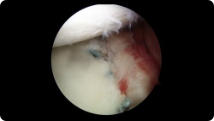

Arthroscopic image of a miniscus tear Arthroscopic image of a miniscus tear after knee arthroscopy

Miniscus Tear